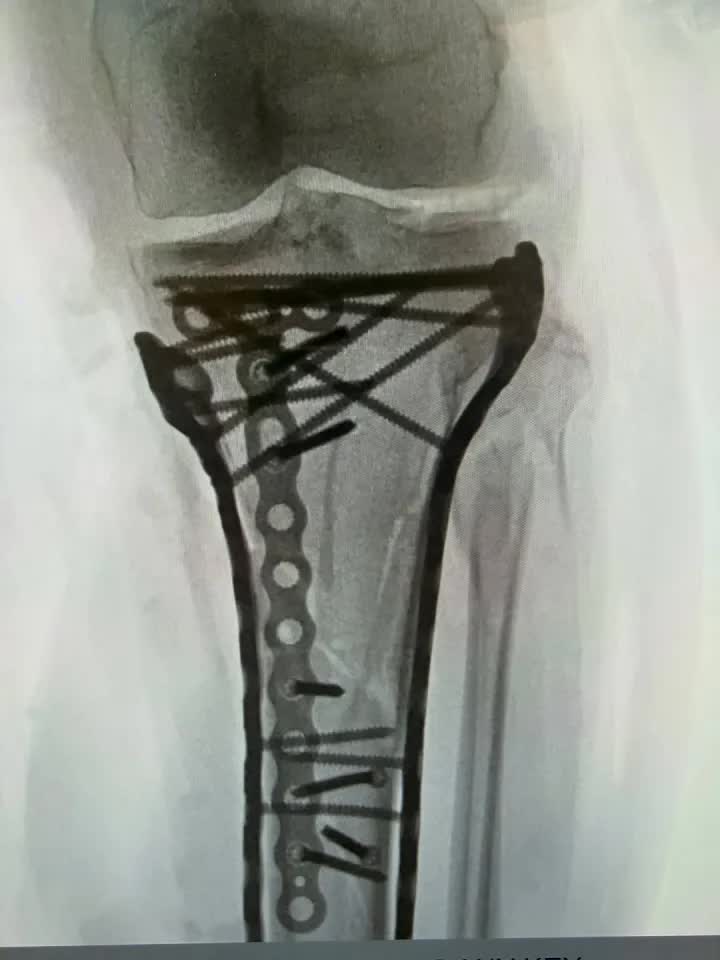

Ngay lập tức, một chiếc trực thăng cứu hộ đã đưa cô thẳng đến bệnh viện. Kết quả chụp chiếu khiến tất cả phải rùng mình: Xương chày bị gãy phức tạp, xương mác và mâm chày vỡ vụn. Nguy hiểm hơn, Lindsey mắc phải hội chứng chèn ép khoang - tình trạng máu tích tụ cực độ nghiền nát cơ bắp và dây thần kinh, buộc các bác sĩ phải đứng trước quyết định giữ hay bỏ đôi chân của cô.

Vonn đã trải qua một ca phẫu thuật lớn để điều trị vết gãy xương "phức tạp" (Nguồn ảnh: instagram @lindseyvonn)

Sau 2 tuần "chiến đấu" trong bệnh viện với những ca phẫu thuật kéo dài 6 tiếng đồng hồ, Lindsey Vonn vừa chính thức được xuất viện. Cô nghẹn ngào chia sẻ trên mạng xã hội: "Đây là điều khắc nghiệt và đau đớn nhất tôi từng đối mặt, nhân lên 100 lần. Bác sĩ Tom Hackett đã cứu mạng tôi, ông ấy đã thực hiện phẫu thuật mở cả hai bên chân để cơ bắp được 'thở', cứu tôi khỏi thảm cảnh phải cắt bỏ đôi chân của mình".